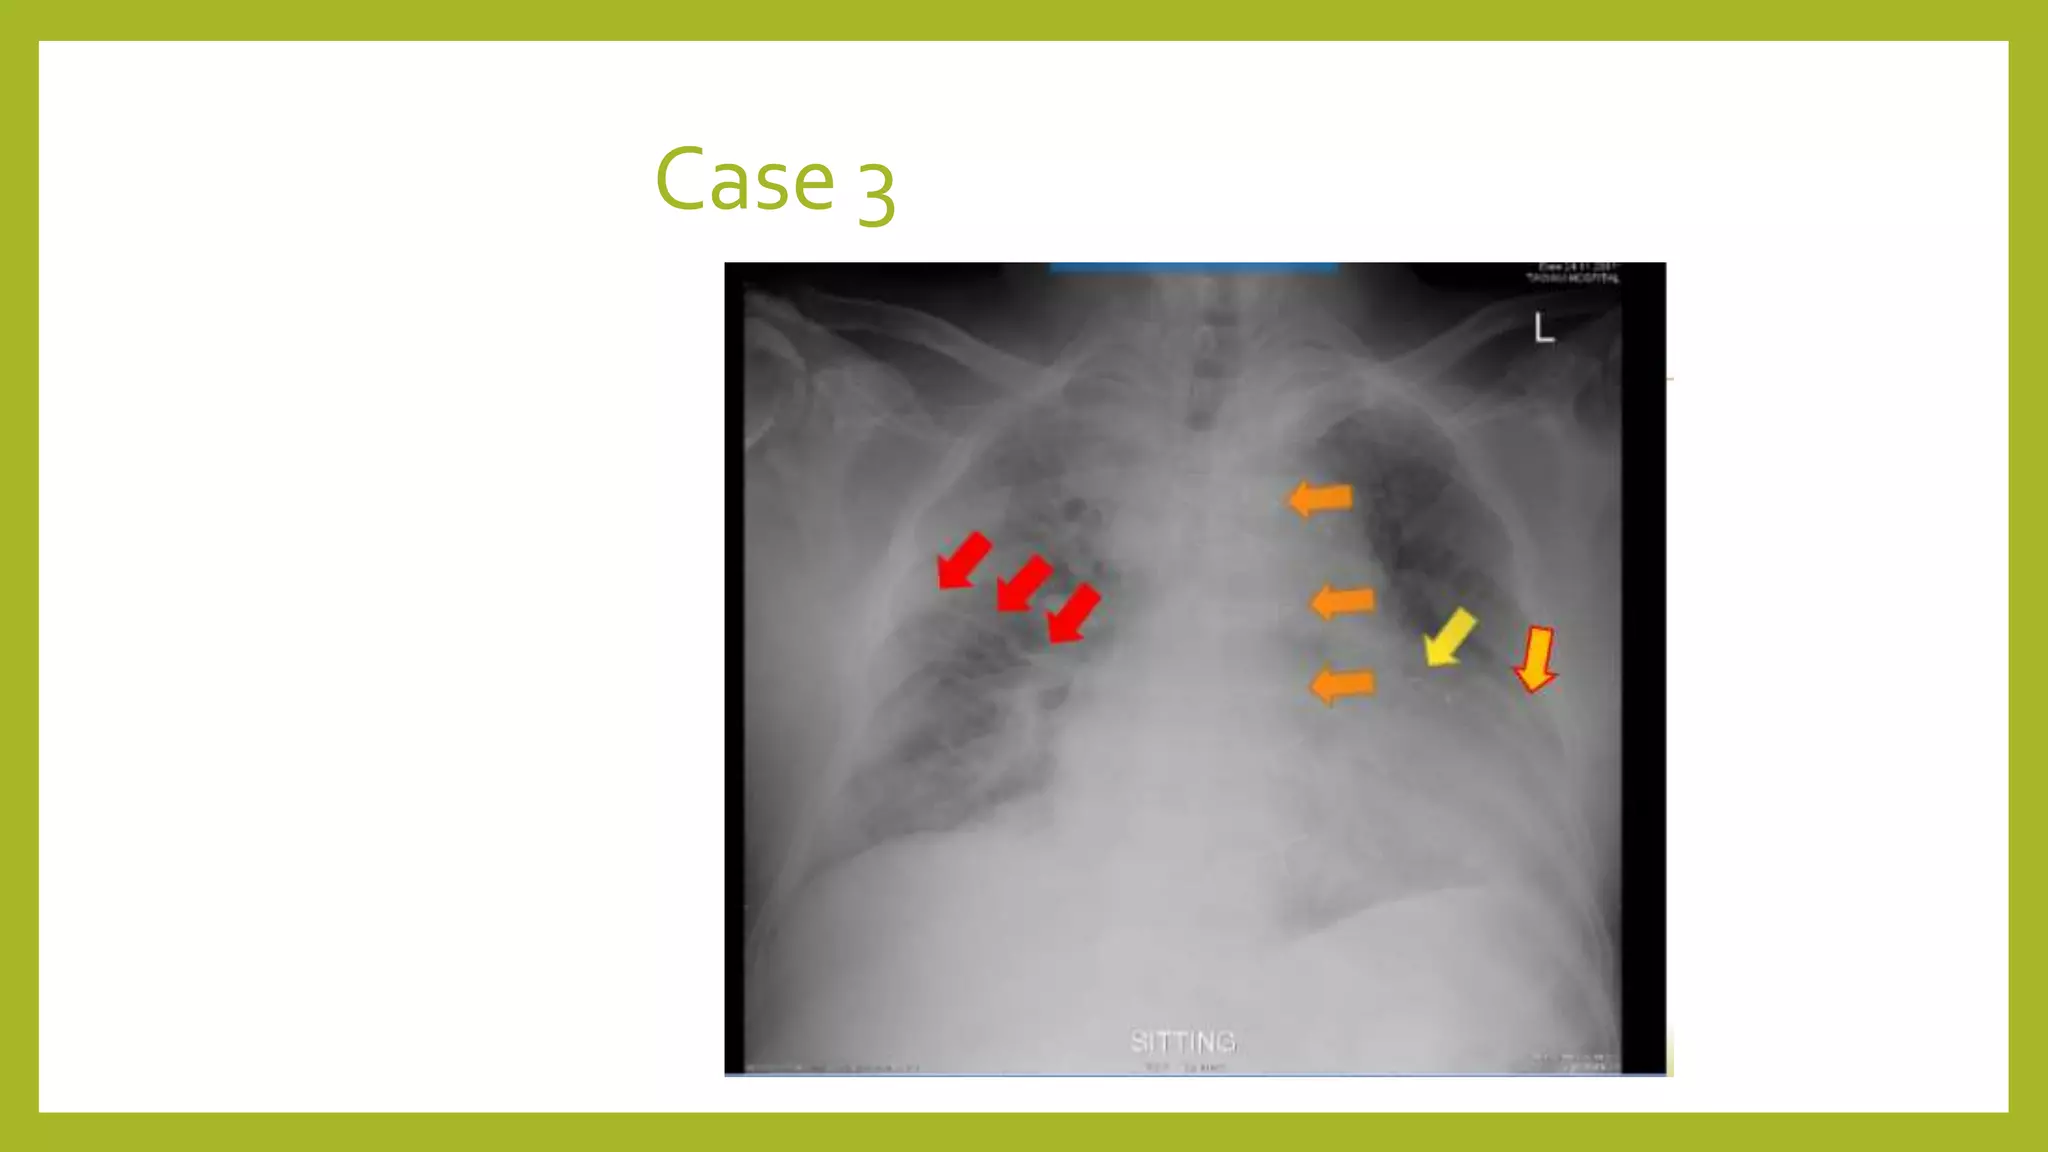

The document provides guidance on approaching and interpreting chest x-rays (CXR). It outlines steps to check the name, date and quality of the film, systematically scan the CXR looking for abnormalities, and determine if the lungs appear too white or black. Specific signs are described to help localize abnormalities, including the cardiac silhouette sign and pleural effusion signs. Examples are given of respiratory distress syndrome, tetralogy of fallot, transposition of great arteries, and total anomalous pulmonary venous return. The take home message is to summarize positive findings, compare to prior CXRs if available, and confirm findings with a radiologist.